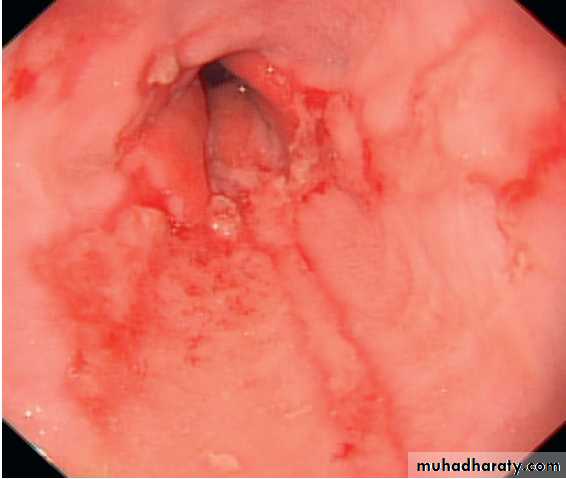

Severe reflux oesophagitis.

There is near-circumferentialsuperficial ulceration and inflammation extending up the gullet.